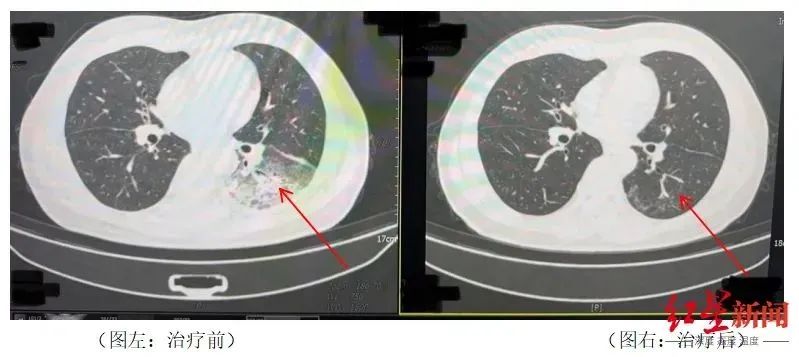

空调吹了三天后,李先生出现了肌肉疼痛、头痛、发烧和咳嗽等症状。一开始我以为是吹空调感冒了,自己吃了感冒药,但是病情没有好转,反而越来越严重。当家人看到这一幕时,他立即被送往医院。胸部CT显示,李先生的左肺已经出现了大面积的白色图像,几乎占据了肺的一半。经检测,最终确认为嗜肺军团菌肺炎。

治疗前后陈先生肺部CT影像